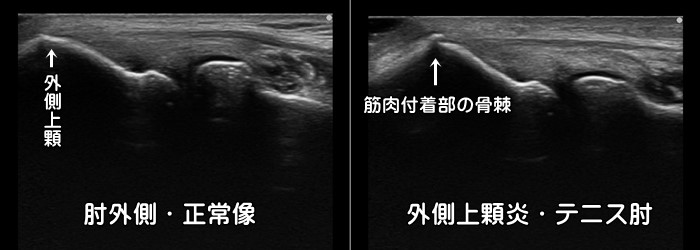

外側上顆炎・テニス肘

肘の外側に痛みがあれば外側上顆炎(テニス肘)が疑われます。テニス選手に多い障害ですが、重いお鍋やフライパンを持つ主婦の方にも発症します。エコーでは短橈側手根伸筋の付着部の低エコー像と肥厚、外側上顆部の骨棘が見られます。炎症反応の動画はこちらで確認できます。